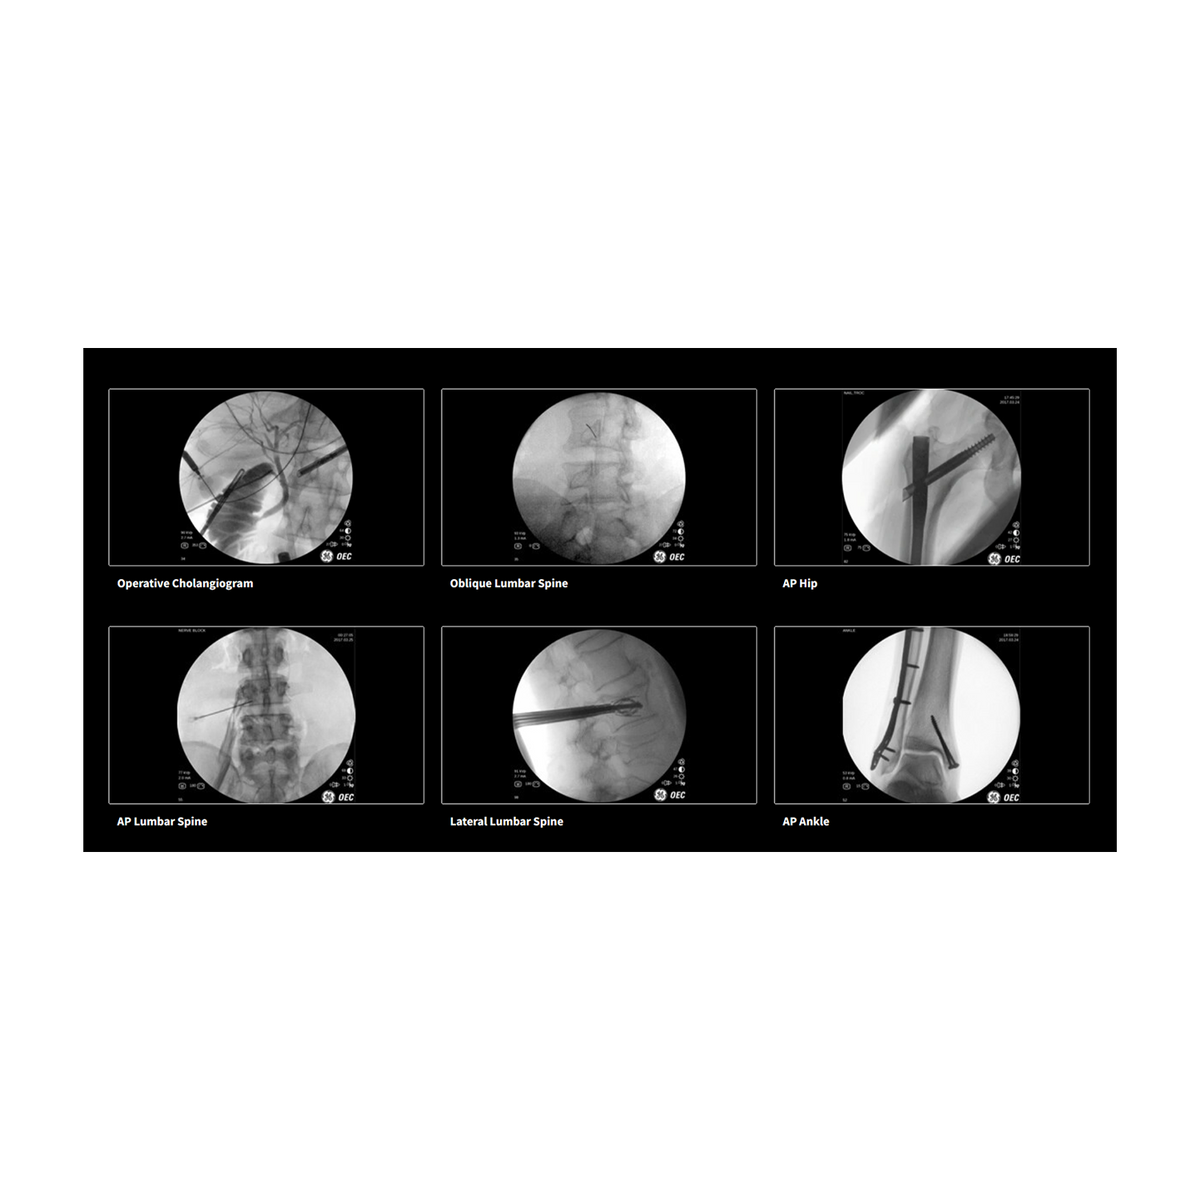

The GE Healthcare OEC One is a comprehensive C-arm system designed to deliver high-quality, Clear View images tailored to the user's needs in various clinical settings. It offers enhanced visibility and the ability to quickly adjust images on the fly.

The OEC One comes in three distinct configurations. The Standard Offering features intelligent automatic software that senses anatomy to provide optimal imaging at the right mA and kV settings. The PM Care Offering is tailored for pain management, providing precise anatomical localization and recording needle positions with real-time digital subtraction angiography (DSA) and cine capabilities up to 8 frames per second. The Vascular Offering is designed for detailed visualization in peripheral vascular and thoracic procedures, capable of highlighting fine details like a .014” guidewire and the sharp edges of vessels during angiography with the aid of Roadmap technology.